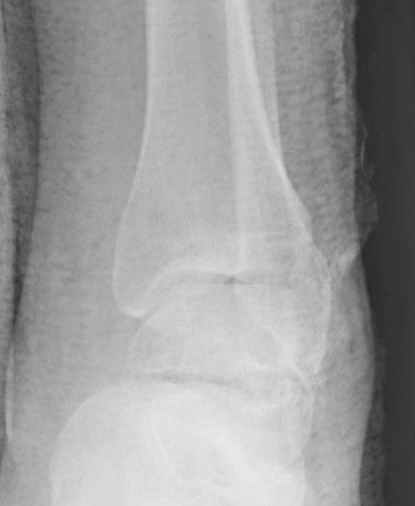

Уважаемые участники русского Ортофорума, поздравляю всех со всеми прошедшими праздниками: Новым годом, Рождеством, Hanukkah, Kwanzaa, желаю участникам всего наилучшего и здоровья.Повреждение таранной кости.Больной 81г автоавария, повреждение таранной кости, здесь снимки. Какие рекомендации?Djoldas Kuldjanov, MDDepartment of Orthopedic SurgerySt. Louis University Medical Center

Вдогонку по поводу перелома таранной кости, больная 81, не страдает диабетом, перелом закрытый, в первый же день поступления ограничились временным наружным фиксатором (как на снимке).